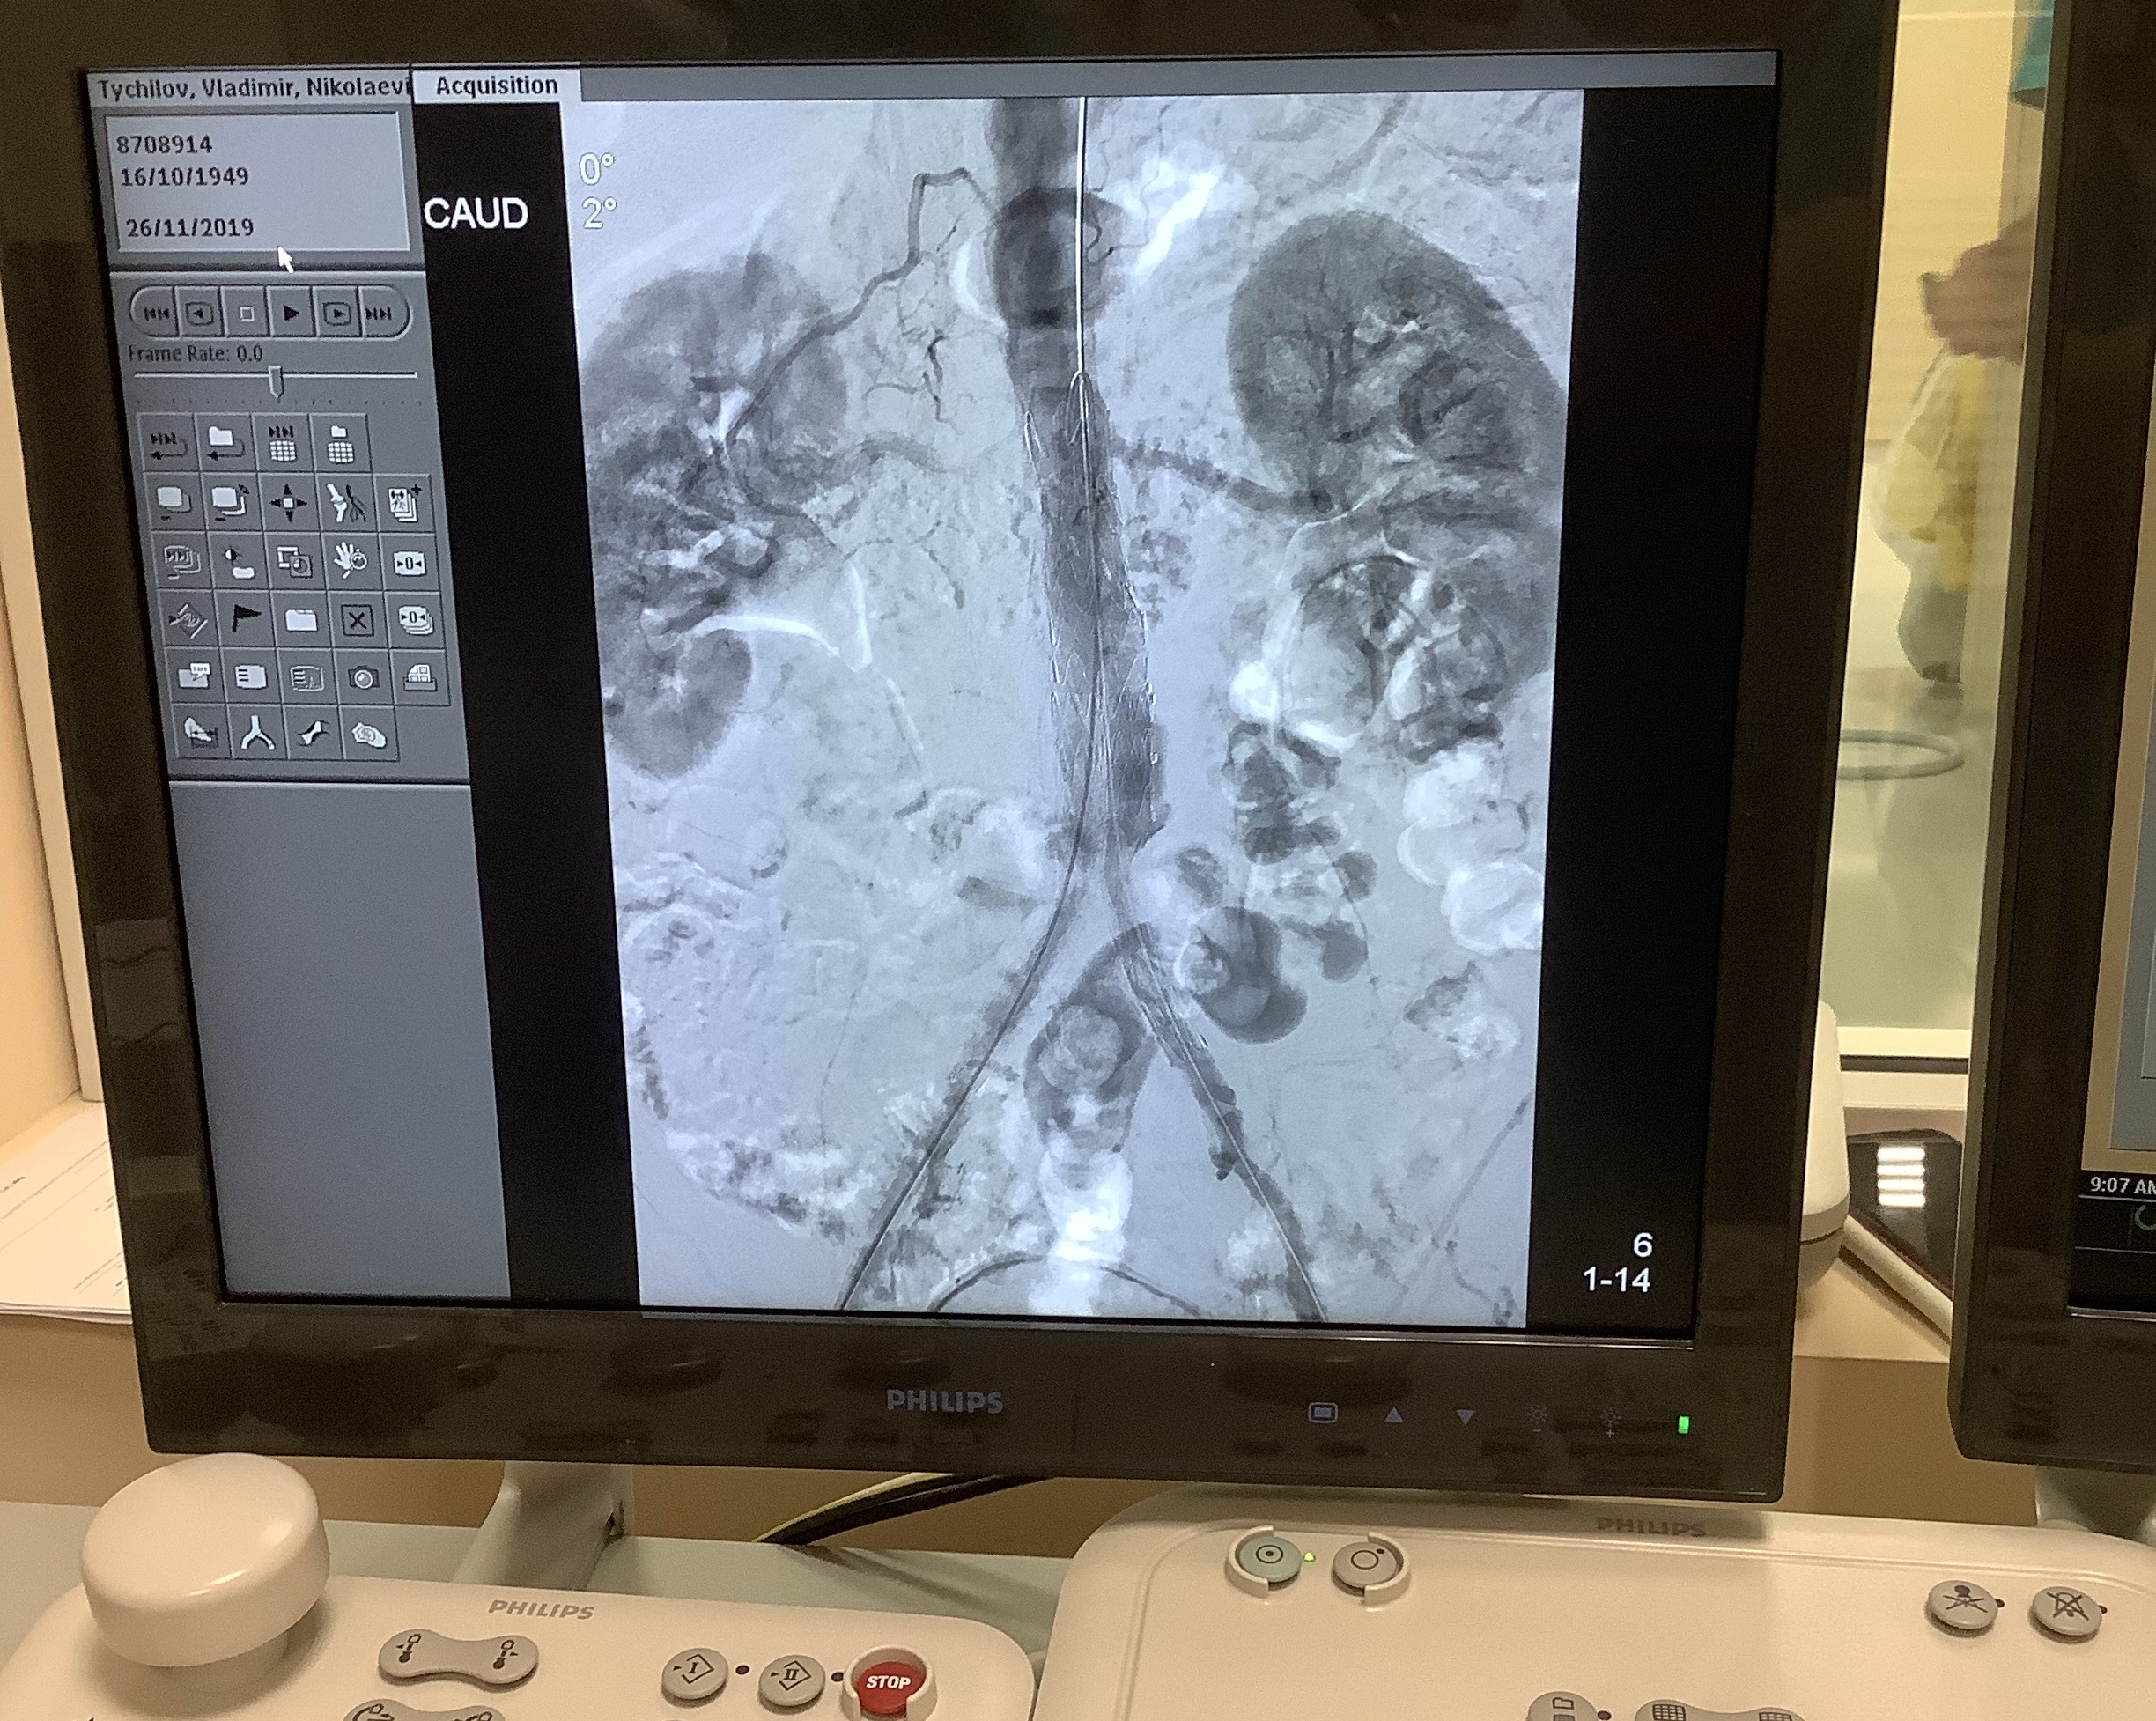

Сегодня утром в городской клинической больнице №7 г.Казани впервые в Республике Татарстан провели операцию по установке уникального стент графта - Ankura AAA от компании Lifetech Scientific (Китай). Операцию провели заведующий отделением сосудистой хирургии Национального центра сердечно-сосудистых заболеваний (Китай), профессор Чанг Шу и заведующий отделением сосудистой хирургии ГКБ 7 г.Казани Ильдар Халилов.

Стент - графт ААА устанавливается при аневризме брюшной аорты. Данный стент-графт уникален, имеет материал покрытия - двухслойную мембрану E-PTFE. Стент-графт уже успешно имплантируется докторами крупных сердечно - сосудистых центров России. В Татарстане установлен впервые.